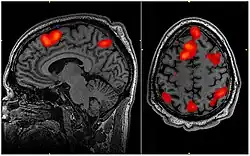

A audiologia é um ramo da ciência que estuda a audição, seu equilíbrio e distúrbios relacionados. Os profissionais com formação em fonoaudiologia, que tratam pessoas com perda auditiva e, de forma proativa, evitam possíveis danos a audição. O Audiologista é o fonoaudiólogo especialista que se dedica ao estudo do sentido audição, desde a recepção das ondas sonoras pelo ouvido até o completo processamento das informações auditivas pelo córtex do sistema nervoso central, dedicando-se ao estudo da anatomia, da fisiologia, da neurofisiologia e das patologias de todo o aparelho auditivo.[5] Este profissional sem dúvida, é o mais capacitado para diagnosticar, atestar e tratar os distúrbios da audição e suas consequências no dia-a-dia do indivíduo por eles acometido, daí o porquê vem sendo muito requisitado na esfera do poder judiciário para que realize perícias nas questões que envolvem a audição, pois, para o judiciário não basta saber que há lesão e o seu grau, é fundamental para a decisão do Juiz saber de que forma aquela lesão afeta a vida do cidadão.[6]

Portanto, o Fonoaudiólogo especialista nesta área, realiza diagnósticos, prognósticos e estabelece tratamentos ou auxilia no estabelecimento de condutas de outros profissionais da área da saúde tais como pediatras, otorrinolaringologistas, neurologistas, neurocirurgiões, geriatras, clínicos gerais e outros. O profissional da saúde, também dedica-se ao estudo de física, acústica e psicoacústica, fundamentais para que possa compreender o funcionamento eletrônico complexo das próteses auditivas, o que o habilita a selecionar, ajustar, regular e adaptar aparelhos auditivos de forma precisa, para corrigir a função auditiva afetada por diferentes graus e formas de lesões, de pessoas em todas as faixas de idade a partir dos primeiros meses de vida. Este profissional é fundamental em todos os níveis de atenção à saúde, desde a atenção básica, passando pela média até a alta complexidade.[7]

O Audiologista é por vezes confundido com o Otorrinolaringologista, que é o especialista que se dedica ao estudo do ouvido, não tendo seu espectro de estudo ampliado para todos os aspectos do sentido da audição, seu processamento e suas influências no processo de linguagem e comunicação humana. O Audiologista realiza exames audiológicos e otoneurológicos -audiometria tonal limiar(via aérea e óssea), logoaudiometria(limiar de reconhecimento de fala, limiar de detecção de fala, índice de reconhecimento de fala e índice porcentual de reconhecimento de fala), audiometria vocal, imitânciometria acústica, provas de função tubária, teste de reflexos neurológicos estapedianos, emissões otoacústicas transientes e evocadas por produto de distorção, audiometria de tronco encefálico, potenciais evocados de curta, média e de longa latência, monitoração transoperatória em neurocirurgias, vídeonistagmografia comum e infravermelha, vectoeletronistagmografia, rinometria acústica, exames de processamento auditivo central (avaliação de como o sistema nervoso central está processando a audição, dentre outros) para verificar se a função auditiva dos pacientes está dentro do padrão normal ou se apresenta algum tipo de alteração.

2 - Linguagem

Acompanha o desenvolvimento do bebê desde o nascimento, e a partir daí em consultas regulares, nos aspectos relacionados ao processo de aquisição e desenvolvimento da linguagem. Estuda problemas relacionados com a aquisição e o desenvolvimento da linguagem, faz diagnósticos de atrasos ou alterações de linguagem, estabelece o tratamento para a habilitação dessas crianças. Faz avaliação, diagnóstico, prognósticos e estabelece tratamentos para pacientes que adquiriram a linguagem mas a perderam ou passam a apresentar algum distúrbio ou anormalidade por algum motivo, a exemplo de quem sofreu derrame cerebral também chamado de AVE (acidente vascular encefálico), traumas cranianos, isquemias cerebrais, doenças degenerativas do sistema nervoso central (esclerose múltipla, mal de Alzheimer, degeneração olivopontocerebelar, mal de Parkinson, etc.), tumores intracranianos, sequelas de neurocirurgias e outras condições clínicas. Essas dificuldades na aquisição da linguagem, interferem também no desenvolvimento da escrita.[8]

11 - Neuropsicologia

O Fonoaudiólogo Especialista em Neuropsicologia está apto a prevenir, avaliar, tratar e gerenciar os distúrbios que afetam a comunicação humana e sua interface com a cognição, relacionando-a com o funcionamento cerebral.[25] Este profissional pode atuar na reabilitação das habilidades cognitivas que direta ou indiretamente se relacionam com a capacidade humana de se comunicar, trazendo de forma funcional ao dia a dia do paciente o uso dessas, por exemplo memorizar lista de compras, ir ao mercado, fazer as compras, paga-las e leva-las para casa, trabalhando habilidades como memória, planejamento e iniciativa.[27]